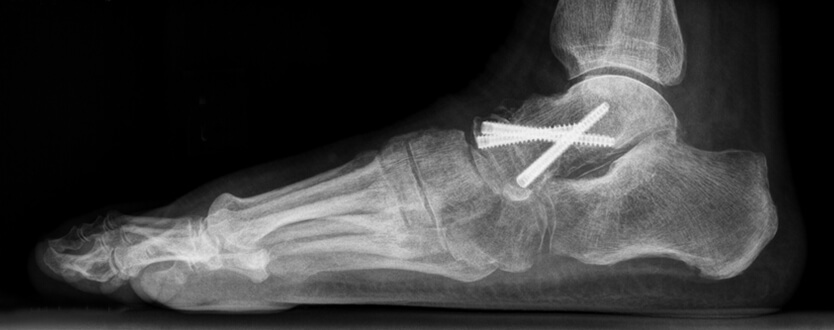

Tijdens de operatie wordt een snee in de huid gemaakt aan de buitenzijde van de enkel. Het beschadigde kraakbeen van het gewricht wordt volledig verwijderd. Vervolgens worden de botten stevig aan elkaar bevestigd met één of meerdere schroeven. In gevallen waarin veel bot is aangetast door de artrose, kan soms een bottransplantatie nodig zijn. Hierbij zal de specialist waarschijnlijk een stukje van uw eigen bot gebruiken, meestal uit uw onderbeen, hielbeen of bekken.

Op de röntgenfoto's ziet u dat het sprongbeen met drie schoeven aan de talus is vastgezet.